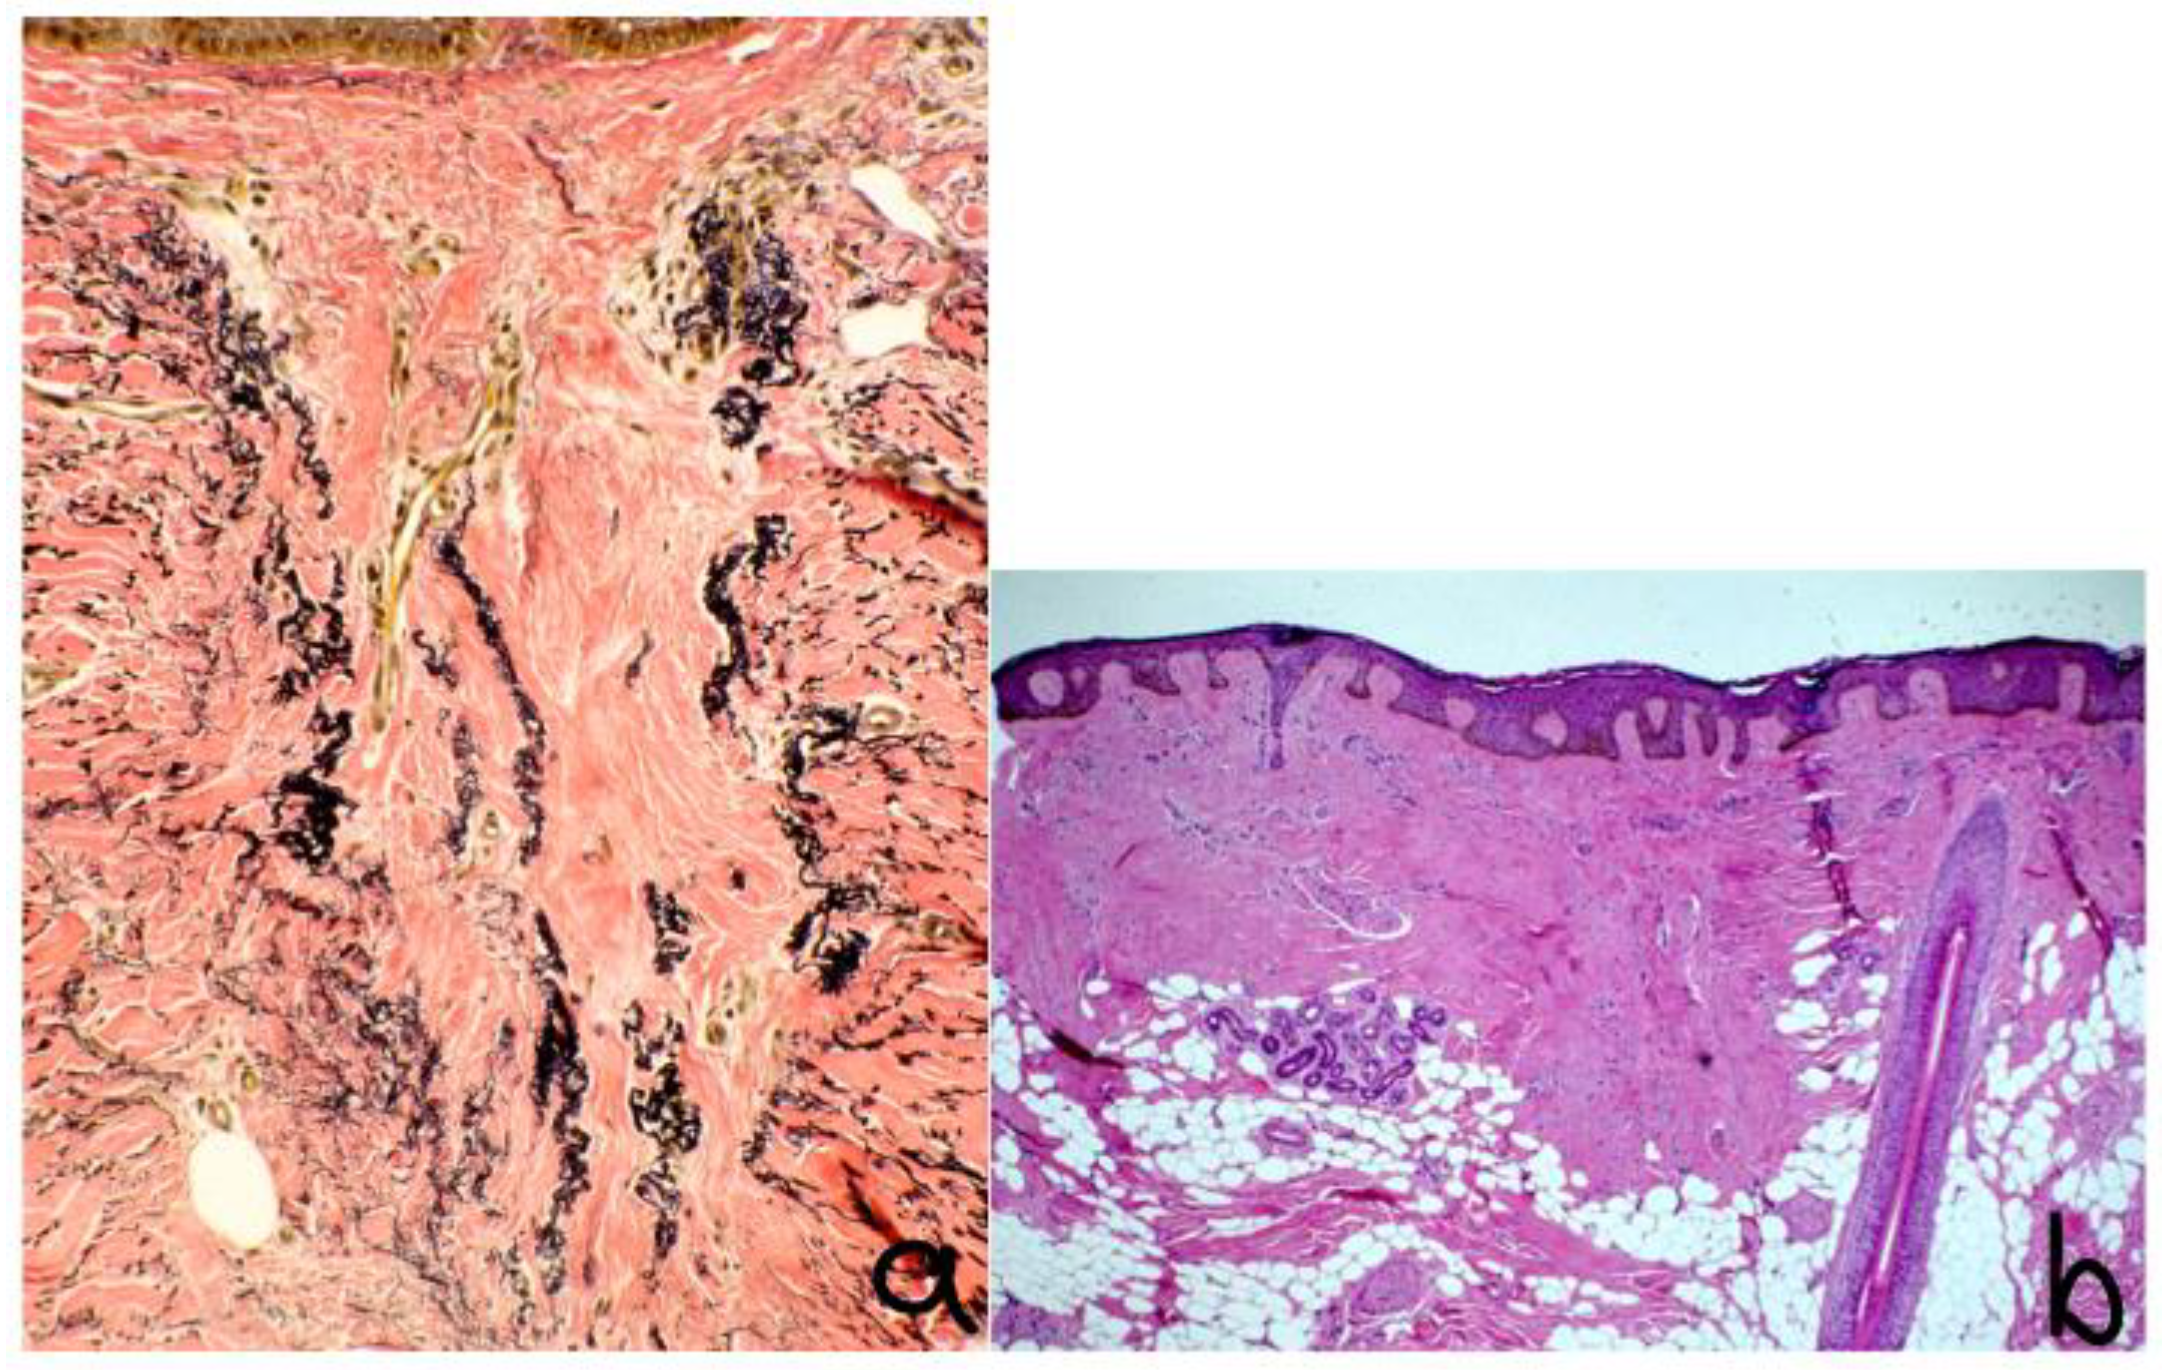

6. Histopathology and Dermoscopy

- Reduced follicular density with altered architecture because of absent or reduced and miniaturised sebaceous glands [16];

- Premature desquamation of the inner root sheath (very sensitive for CCCA, even in the absence of other findings) [16];

- Lamellar hyperkeratosis or parakeratosis [16];

- Naked hair shafts in the dermis [16];

- Follicular miniaturisation [16];

- Increased distance between affected follicles and small blood vessel clusters (BVCs; i.e., the perifollicular mucinous fibroplasia from chronic inflammation results in diminished blood supply [9].